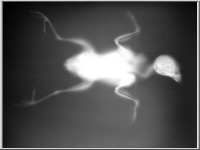

A képekre kattintva a röntgenfelvételek üveglemezeinek reprodukcióit, a kis képek jobb felső sarka melletti ikonokra klikkelve pedig az üveglemezeket védő, Gothard által feliratozott, a felvételek adatait tartalmazó borítékok reprodukcióit láthatjuk.

Az 1. sorszámú lemez elveszett, csak papírmásolat maradt fenn róla. A 25. és 26. sorszámú borítékok 2-2 felvételt tartalmaznak (itt a-val és b-vel jelölve), míg a 32. sorszámú lemez eltört, két darabban van.